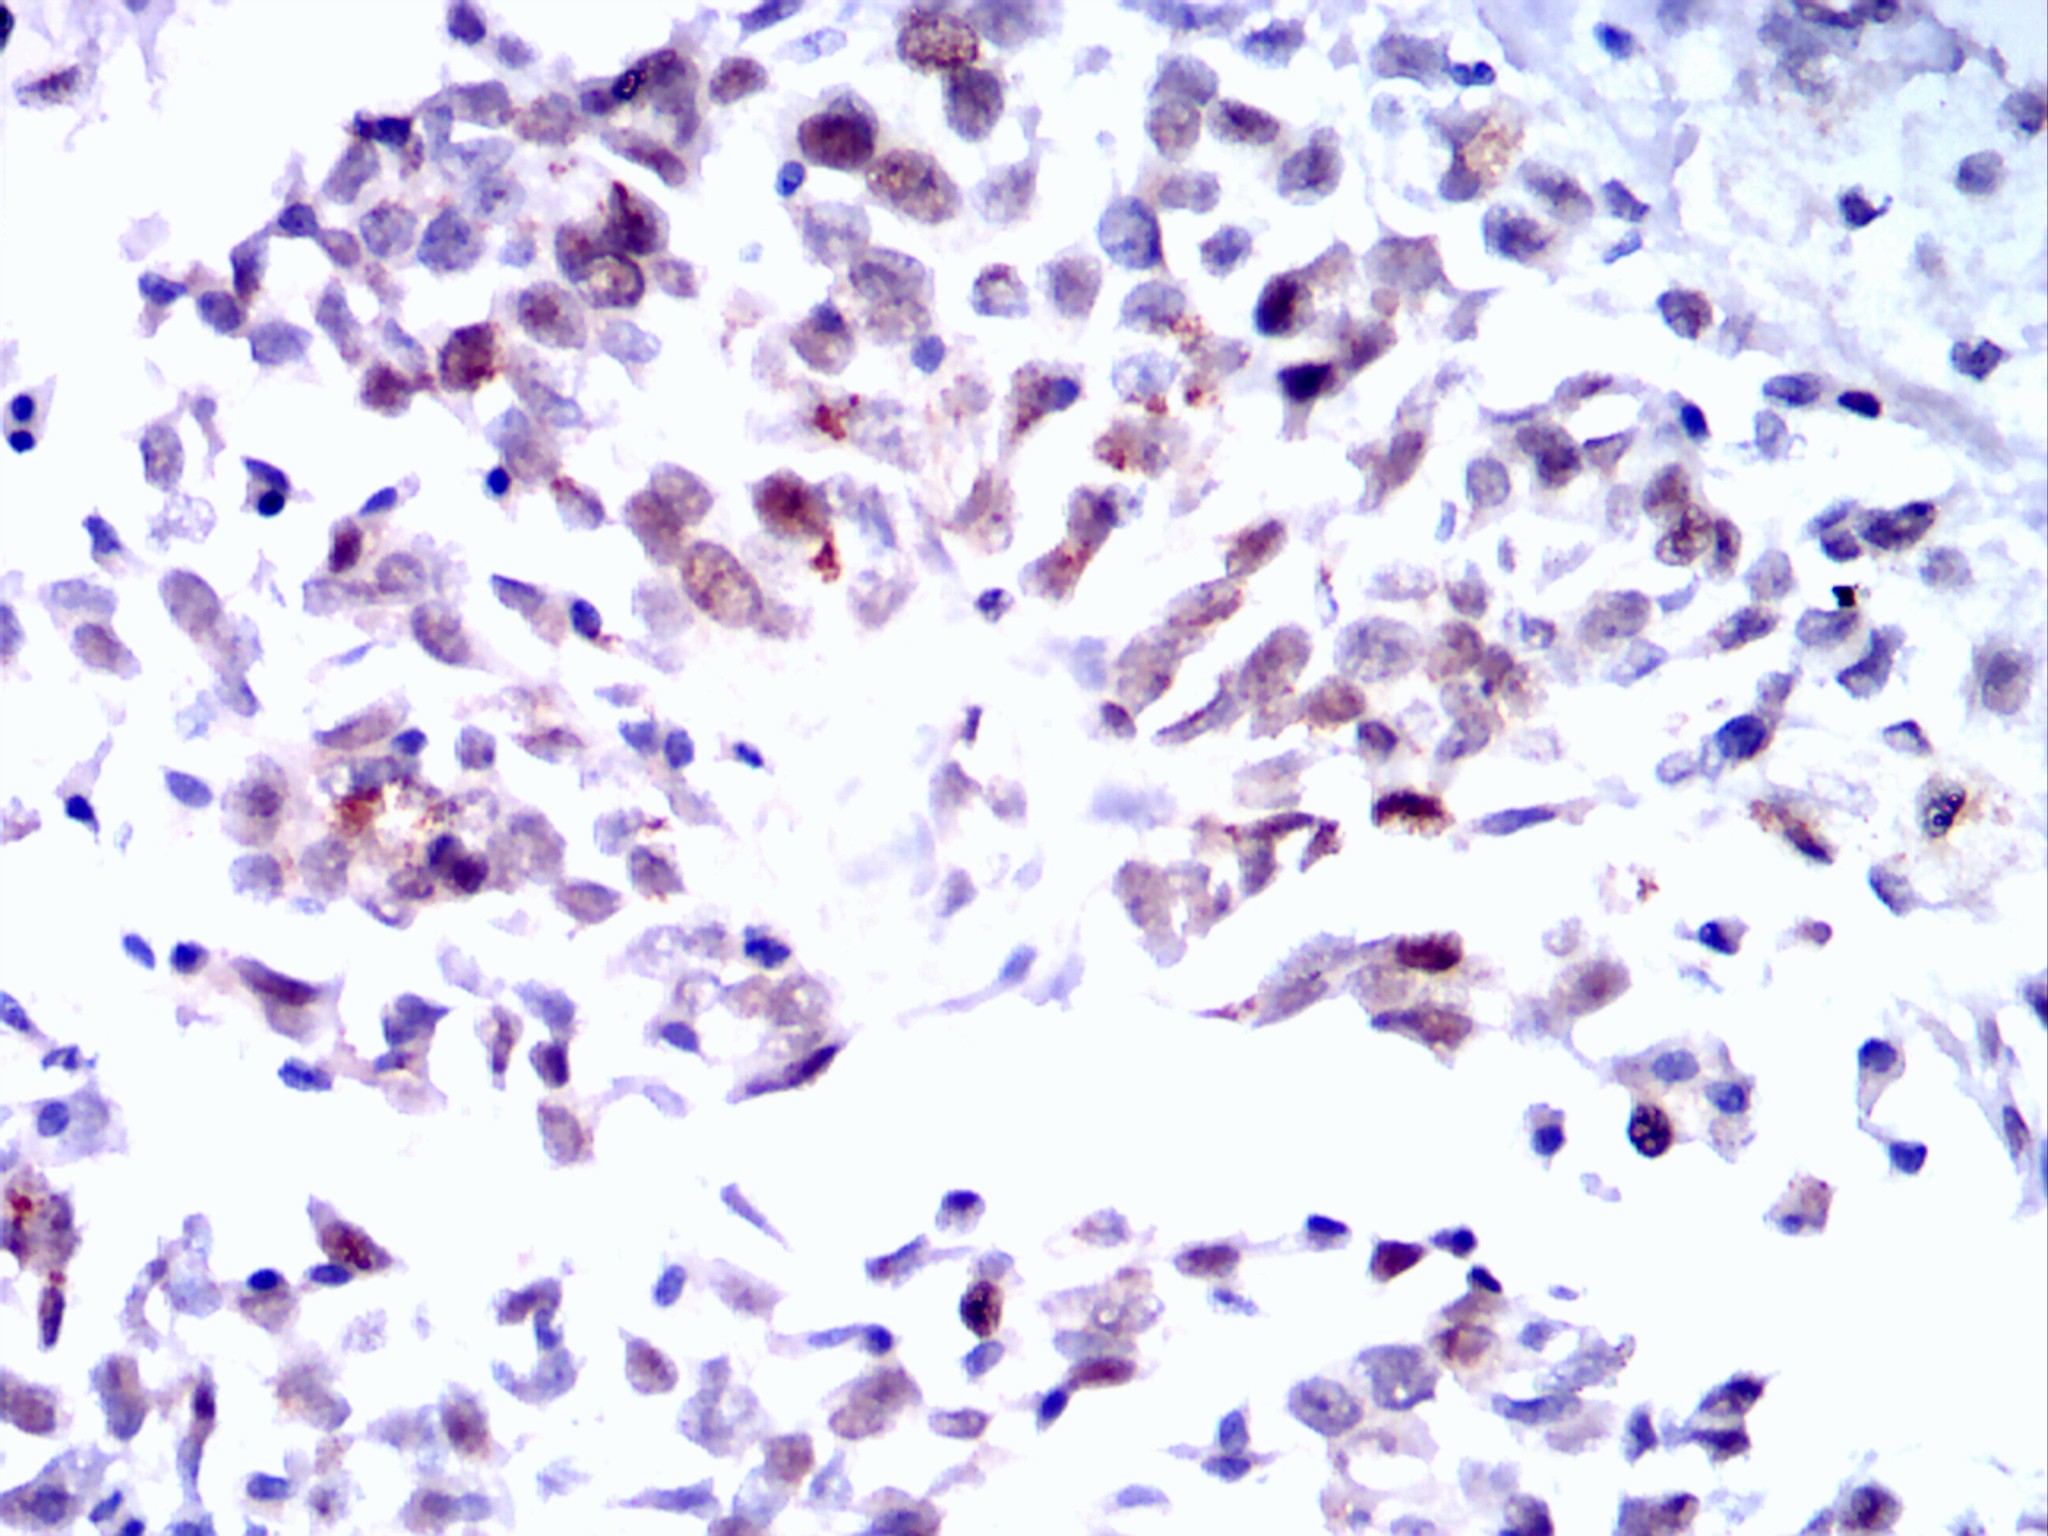

分类: 科研抗体货号: 20092别名: ERK; p38; p40; p41; ERT1; MAPK2; PRKM1; P42MAPK; p41mapk; MAPK1应用: WB,IHC,IF反应种属: Human,Mouse,Monkey